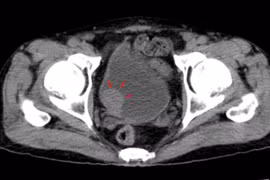

U bàng quang là loại u thường gặp trong các loại u ở đường tiết niệu. Theo thống kê, ung thư bàng quang là bệnh lý đứng thứ hai sau ung thư tiền liệt tuyến thuộc hệ tiết niệu sinh dục.